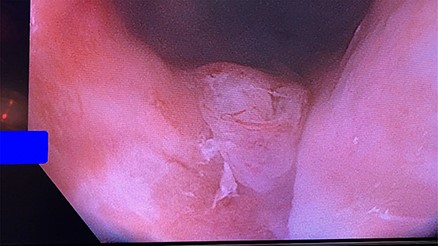

Flexible sigmoidoscopy demonstrating granulation tissue at the posterior aspect of the distal rectum.

After 8 weeks, the patient was taken for repeat examination under anesthesia and flexible sigmoidoscopy. There was a significant improvement in the severity of his Crohn’s colitis. The rectal perforation had closed (Fig. 4) and the transperineal wound had completely healed. Once the Crohn’s disease is adequately controlled with medical therapy, the ileostomy will be addressed (Fig 5).